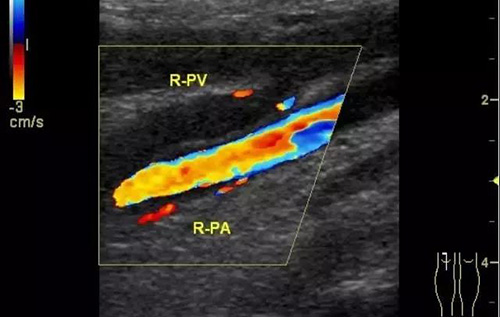

下肢深靜脈血栓形成后綜合征的診斷主要依靠靜脈造影和彩色超聲多普勒,而彩超機具有無創、重復性好、準確率高的優點,逐漸成為診斷此病的首選。

彩色普勒超聲診斷儀,線陣探頭,頻率7.5~10MHz。受檢查者先取仰臥位,患肢髖關節略外旋,大腿輕度外展且膝關節略曲,使整個下肢呈松弛狀態。自上而下順序檢查髂外、股總、股淺、股深及大隱靜脈;之后取俯臥位,檢查靜脈及小腿靜脈。以縱切和橫切顯示血管,灰階超聲主要觀察血管內徑、管壁結構及血栓情況,CDFI主要觀察管腔內有無血流顯示、充盈缺損及血液返流情況,必要時擠壓小腿腓腸肌以利血流顯示。

彩色多普勒超聲具有很高的特異性和敏感性,是超聲診斷技術的重要發展。

彩超診斷下肢深靜脈血栓形成后綜合征具有無創、實時、動態、重復性好、準確率高的特點,且能充分了解血管內外的解剖學改變,觀察靜脈管壁、血流充盈、靜脈瓣返流程度以及側支循環是否建立和血栓的溶液情況,可直觀地觀察到血流動力學改變,所以具有很高的使用價值。通過對治療前后聲像圖的對比,可以提示臨床的治療效果,對于臨床治療具有很大的指導作用。